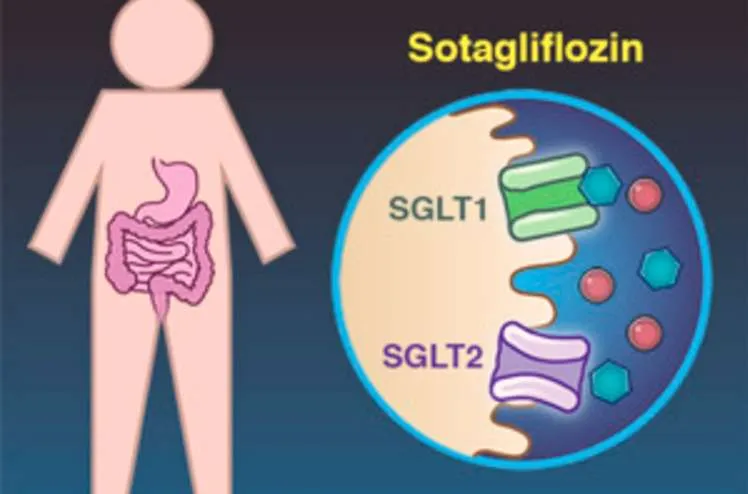

Descubra como o sotagliflozina pode mudar o manejo de um caso de hipomagnesemia severa e refratária. Saiba mais sobre este avanço terapêutico e seu impacto prático na nefrologia moderna!

Valkercyo Feitosa